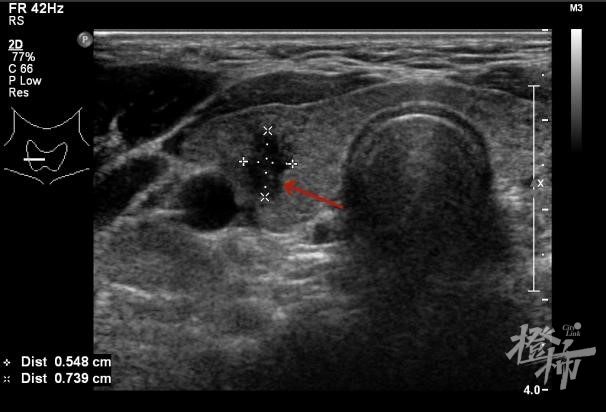

超声检查提示一个5.48mm×7.39mm左右大小的结节 医院供图